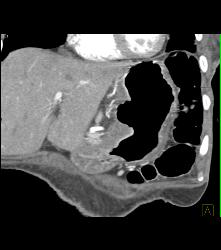

Gastric Carcinoma